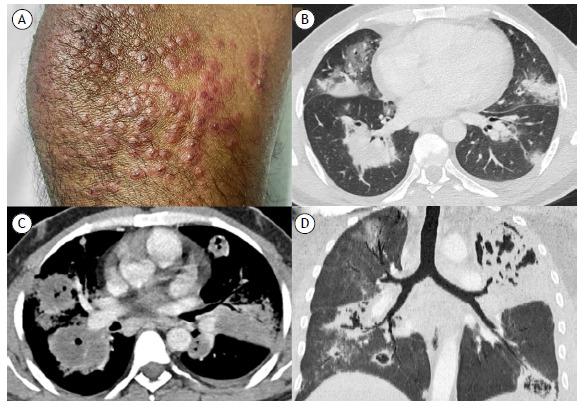

肉芽肿伴多血管炎。

Granulomatosis with polyangiitis.